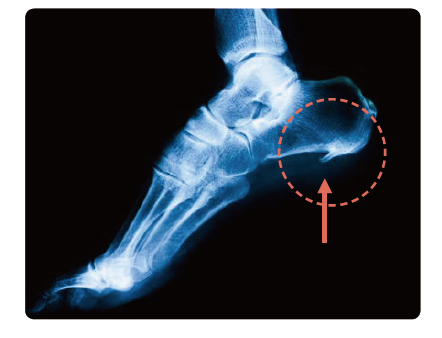

장시간 서있고 많이 걸으시는 분들에게 자주 발생하는 족저근막염에 대해 알아보겠습니다.

발바닥 근막염(Plantar Fasciitis)